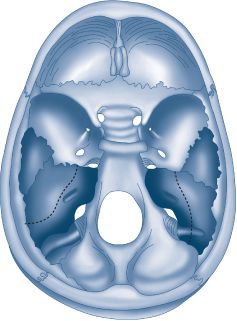

Temporal bone fractures are divided into two patterns (Fig. 18-7), longitudinal and transverse, based on the clinical picture and CT imaging. In practice, most fractures are oblique. By classical descriptions, longitudinal fractures constitute 80% and are associated with lateral skull trauma. Signs and symptoms include conductive hearing loss, ossicular injury, bloody otorrhea, and labyrinthine concussion. The facial nerve is injured in approximately 20% of cases. In contrast, the transverse pattern constitutes only 20% of temporal bone fractures and occurs secondary to fronto-occipital trauma. The facial nerve is injured in 50% of cases. These injuries frequently involve the otic capsule to cause sensorineural hearing loss and loss of vestibular function. Hemotympanum may be observed. A cerebrospinal fluid (CSF) leak must be suspected in temporal bone trauma. This resolves with conservative measures in most cases. The most significant consideration in the management of temporal bone injuries is the status of the facial nerve. Delayed or partial paralysis will almost always resolve with conservative management. However, immediate paralysis that does not recover within 1 week should be considered for nerve decompression. (See Schwartz 9th ed., p 488.)

FIG. 18-7. View of cranial surface of skull base. Longitudinal (left) and transverse (right) temporal bone fractures.